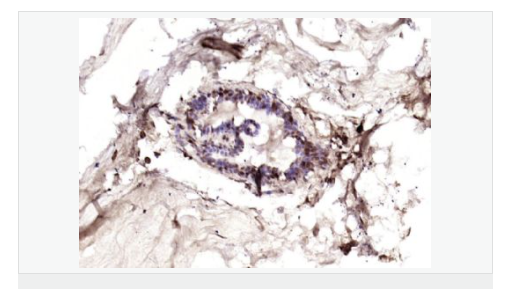

image.png